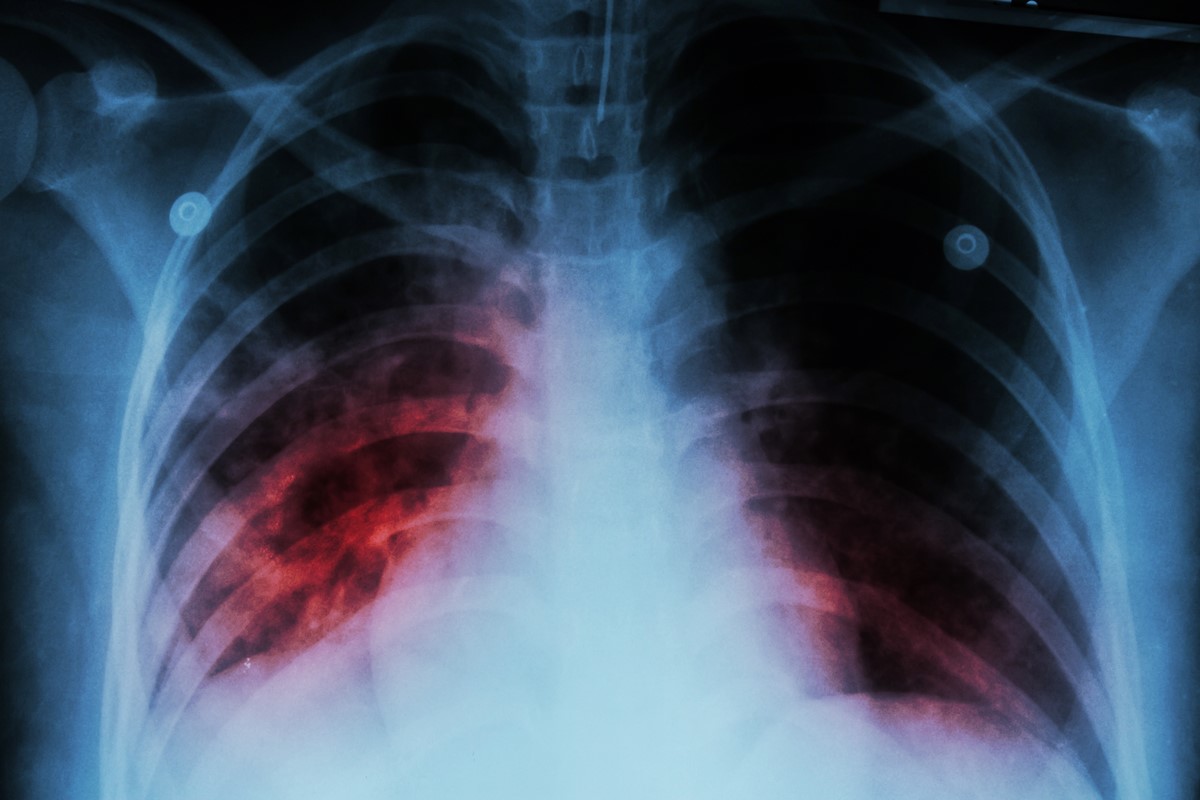

Patients with ILD will have a history of long-term shortness of breath and a non-productive dry cough that does not get better with antibiotics. Patients will be diagnosed quite quickly when they obtain a chest X-ray of their lungs. Patients will ILD will have visible fine lines that are seen in the lung fields.